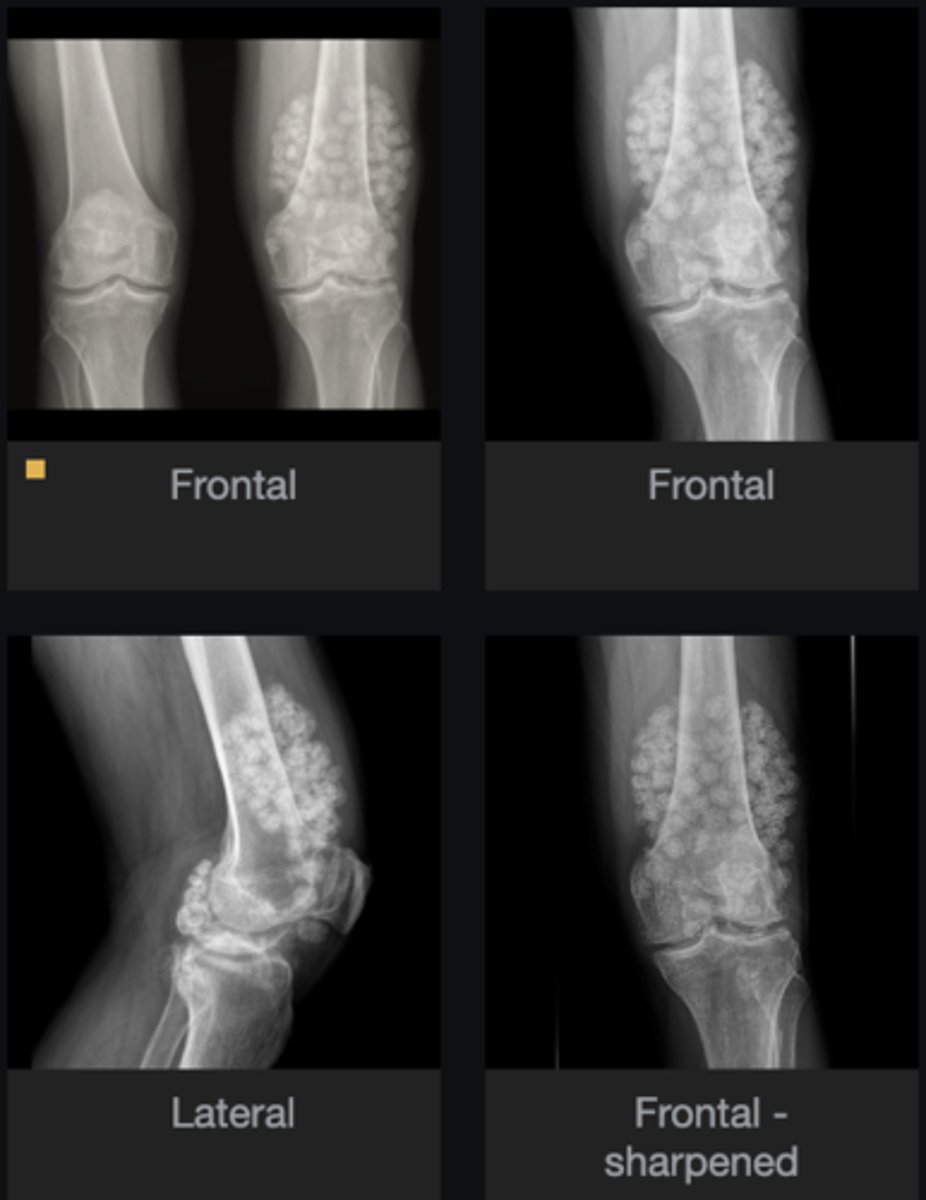

- Subchondral cyst

- Subluxation

- Non-uniform loss of joint space

- Subchondral sclerosis

- Osteophytes

Describe findings

Osteoarthrosis

Diagnosis?